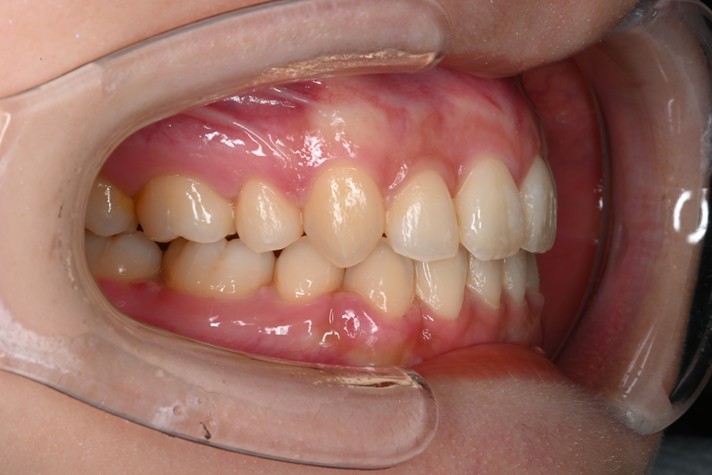

症例3:出っ歯が気になる

| 患者様データ | 20代 女性 |

| 来院主訴 | 出っ歯が気になる。 |

| 治療内容 | 出っ歯を治すために上の小臼歯を2本抜歯し、インビザラインにてマウスピース矯正を開始しました。かみ合わせを整えるためにゴムかけを行いました。 |

| 概算治療費 | 約85万円 |

| 治療期間 | 1年4ヶ月 |

| 通院回数 | 8回 |